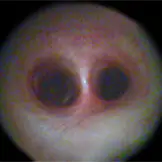

Luftsackendoskopie

Eine Besonderheit der Pferde ist der Luftsack, der eine Aussackung der Ohrtrompete unterhalb der Schädelbasis darstellt. Da der Luftsack über die Ohrtrompete mit dem Nasenrachen in offener Verbindung steht, können Infektionserreger in den Luftsack eindringen. Indikationen für eine Endoskopie der Luftsäcke sind Schwellungen im hinteren Ganaschenbreich sowie einseitiger blutiger oder eitriger Nasenausfluss.